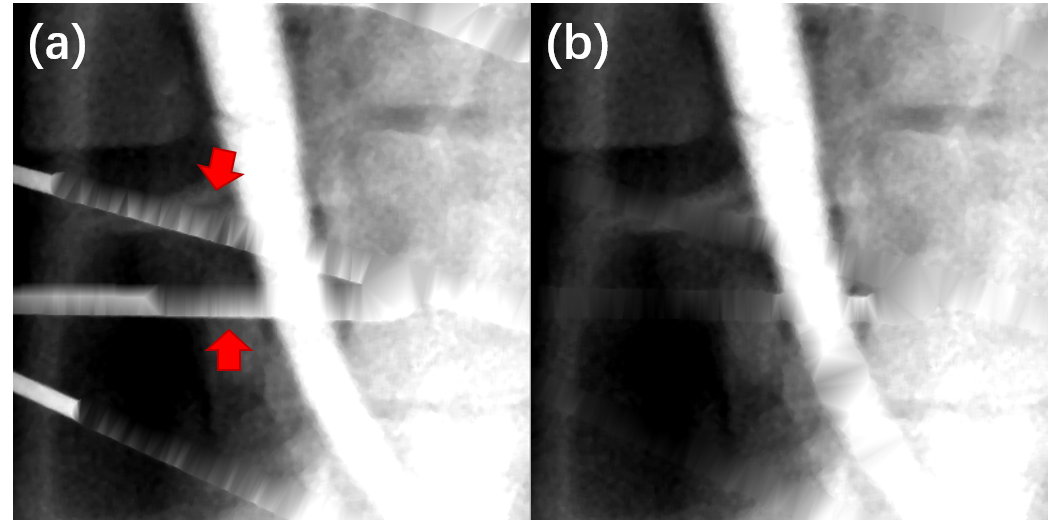

Some K-wires are nearly correctly segmented in the image domain (the right one in Fig. 6 (b1-b4)), but still get slight deviations from the real metal traces in the projection domain after the forward projection. These deviations sometimes come from the geometrical randomness of the entire CBCT system. Triangulation-based interpolation is ineffective in this situation and results in saw-toothed inpainting results (red arrows in Fig. 7 (a)). The saw-toothed projection data further introduces severe streak artifacts to the reconstructed images as a result of ramp filtering (Fig. 6 (b3) as an example). As segmentation in the projection domain is more precise than in the image domain, the proposed method generates interpolation output that is substantially smoother.

Triangulation-based interpolation has been proven effective in multislice helical CT [37, 38], but has hardly been tested on CBCT datasets. In this work, we show that the Delaunay triangulation-based interpolation is a powerful tool in CBCT metal artifact reduction but it depends heavily on the metal trace accuracy. This method may introduce severe secondary artifacts with biased metal traces and result in even worse image quality compared to 1-D linear interpolation. The proposed projection domain segmentation method is an excellent complement to triangulation-based interpolation for providing more precise metal traces.